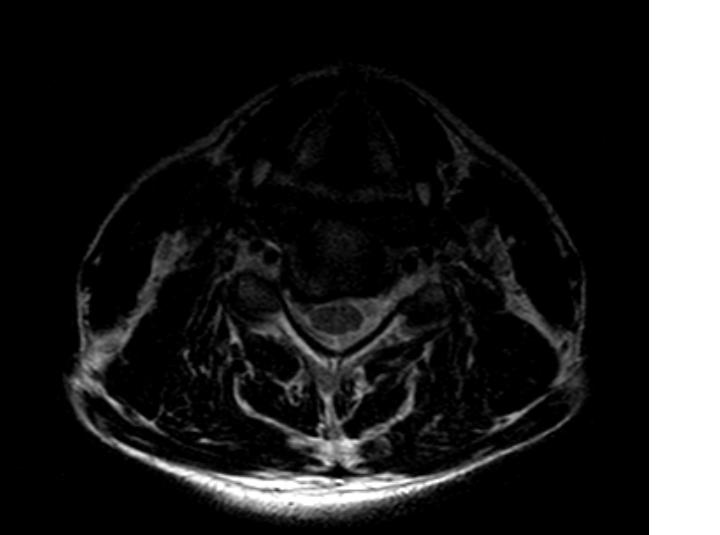

kręgosłup

dyskopatia

dyskopatia kręgosłupa

operacja kręgosłupa